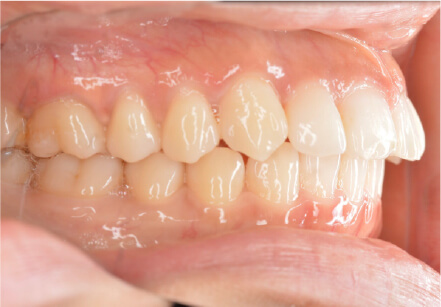

叢生の症例

10歳

/

女性

相談内容

スペース不足

カウンセリング・診断結果

myoからの移行。スペース不足のためインビザライン開始。

治療内容・方法

全額アライナー矯正

術後の経過・現在の様子

クリアライナー使用

治療のリスク

痛み・歯根吸収・歯肉退縮・虫歯・後戻り

費用・治療期間

(インビザのみ)385,000円、1年2ヶ月 + myo3年4ヶ月

トレーニングなど